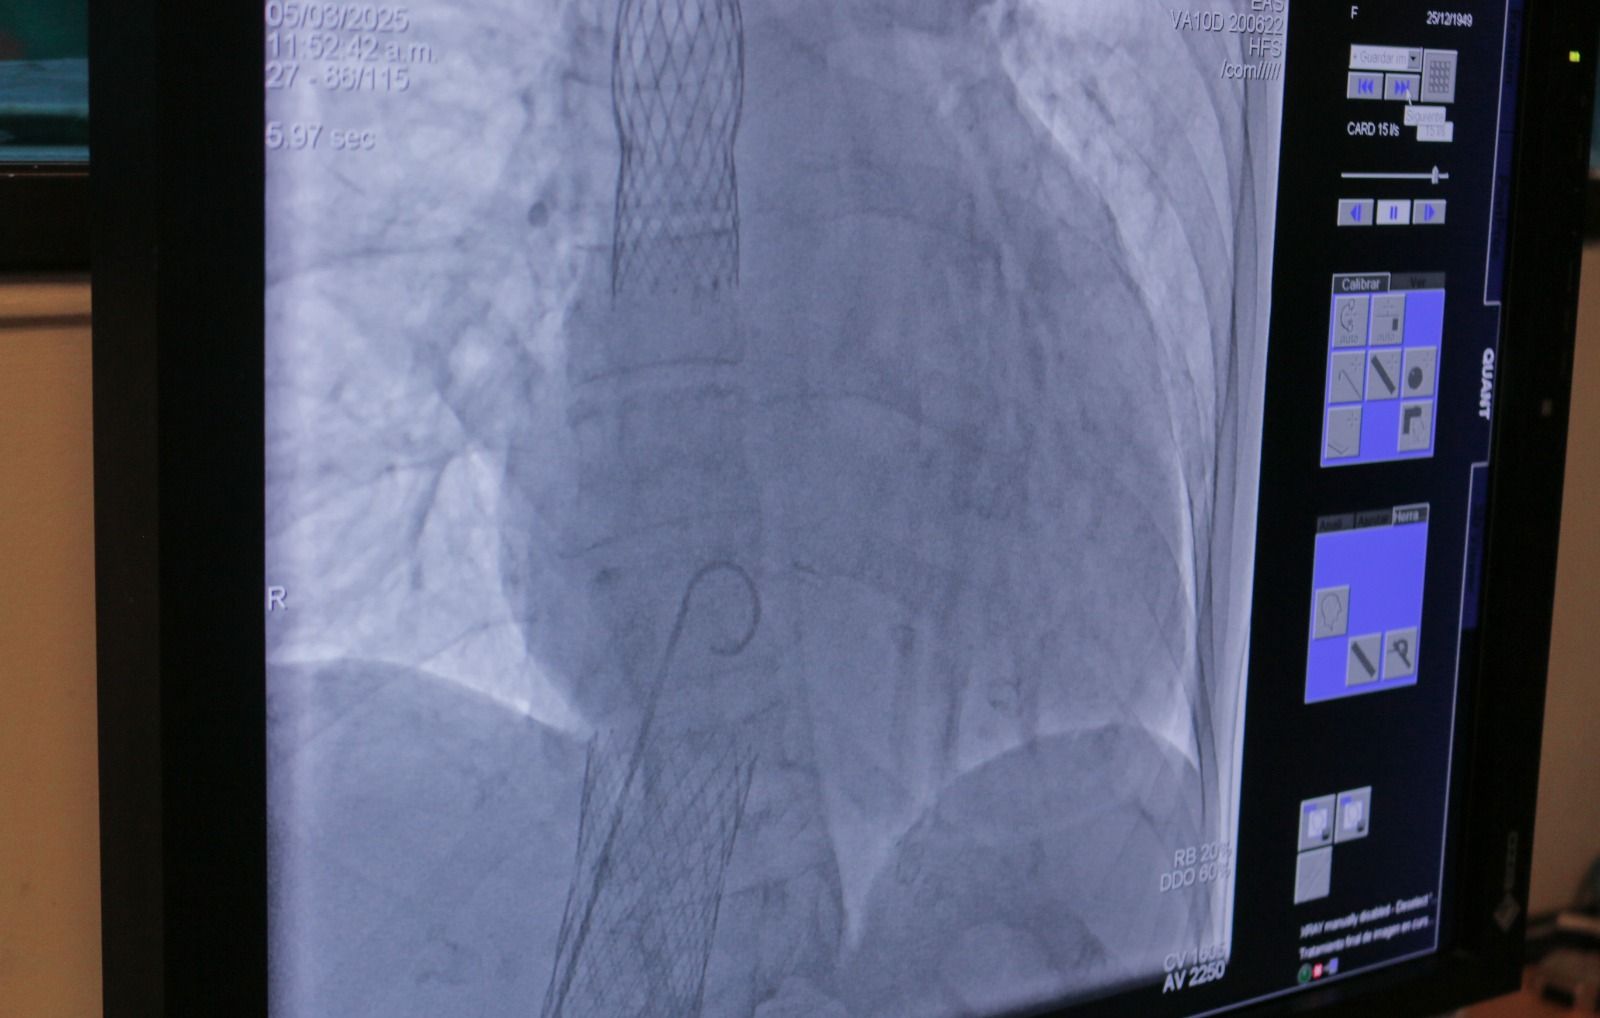

Desde el Servicio de Hemodinamia del Hospital Escuela, el Dr. Ernesto Duarte contó cómo se llevó a cabo esta innovadora cirugía que consiste en la colocación de una válvula aórtica en las venas cavas superior e inferior del corazón del paciente. Este tipo de intervención está especialmente indicada para aquellos que sufren de insuficiencia cardíaca y que han enfrentado múltiples internaciones, con el objetivo de reducir la tasa de hospitalización y mejorar la calidad de vida del paciente.

“Con este implante, buscamos no solo mejorar la sobrevida del paciente, sino también permitir que pueda regresar a su hogar al día siguiente de la intervención”, explicó el Dr. Duarte. La insuficiencia tricuspide, una patología a menudo olvidada, presenta una alta mortalidad quirúrgica, lo que hace que este procedimiento sea aún más valioso, ya que la mortalidad asociada al implante de esta válvula es inferior al 1%.

El Dr. Enzo Moreschi, también parte del equipo médico, destacó que el hospital está realizando estudios sobre la válvula aórtica sin necesidad de cirugía convencional, lo que significa que no se requiere abrir el pecho del paciente. “Este enfoque endovascular permite que los pacientes se beneficien de un procedimiento menos invasivo, con un tiempo de recuperación mucho más rápido”, añadió.